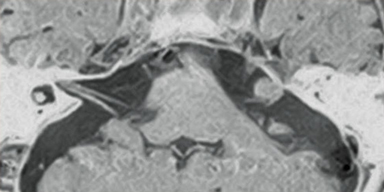

FatSep-T1WI

3D-BASG

The FatSep (fat water separation) function enables imaging of different TE to acquire in-phase and out-of-phase images simultaneously. The two types of images are added to form fat suppressed images. Through this additional process, FatSep provides fat suppressed images with a good SN ratio and clarity. It can also provide a Fat image through a subtraction process.